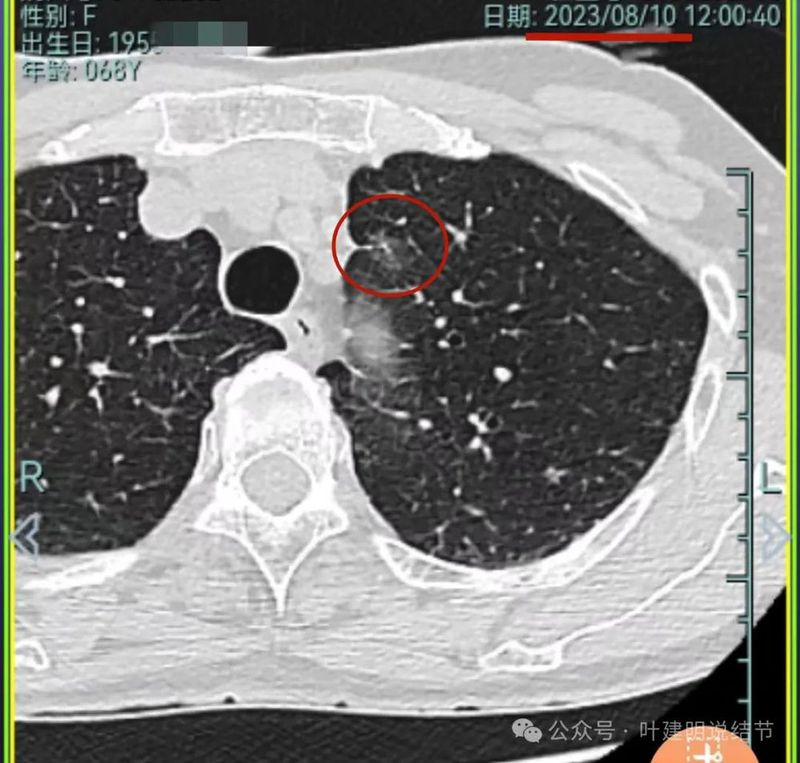

再看2023年8月的影像:

病灶1没什么进展。

病灶1仍磨玻璃稍高密度,有血管进入,大小无显著进展,但密度从开始到现在是有所进展的。

我想我们这样也来考虑问题:1、左侧已经手术的确诊是肿瘤性质,左上已经消融的也是随访持续存在的磨玻璃密度结节,虽然没有病理依据,仍然要考虑广义上来讲的肿瘤范畴,看了以前的片子,从2019年到2023年并没有显著的进展,大概是肺泡上皮不典型增生可能性大。右侧的也有磨玻璃结节与混合磨玻璃结节考虑是肿瘤范畴的。所以总体上两肺多原发早期以磨玻璃为表现的肺癌,整体风险都不大。2019年切除的左肺下叶病灶也是纯磨玻璃密度,其实如果继续随访或者只做楔形切除也并没有什么关系。这说明体质本身或者致病的因素,就是容易长磨玻璃肺癌的,即便把目前发现的都解决,后续仍可能再有新的。原因不明,致病因素仍在。2、右肺上叶红色之处从2019年开始,是逐渐进展的,当然即便是现在,也不是说危险就已经很大,考虑仍然是原位癌或者微浸润性腺癌可能性大;中叶蓝色这处乍一看像至少是微浸润,但前后对比以后发现从2019年到现在,几乎没有显著进展,这样的话慢性炎伴肺泡上皮增生或者伴纤维增生也是有可能的,至少风险并不能认为大;右肺下叶黄色这一处,使纯磨玻璃密度,整体轮廓与边界清楚,考虑是肿瘤范畴的,不典型增生可能性较大,也有可能原位癌,随访稍有进展,风险仍然不大;中叶绿色这处是慢性炎伴钙化的,靠近叶裂的地方也像慢性炎,但此处随访有所进展。不过因为有卫星灶,整体显得比较散,所以虽然恶性可能性较大,但也不能完全除外炎性的可能性。当然如果此灶确实恶性,那风险则相对较其他进展缓慢的要高一些。从目前右侧所在的这些病灶来讲,真正有一定的风险而且最为确切的是红色这处,而且应该也没有到浸润性腺癌或者说不处理会要转移很危险这种程度。3、明确了多原发早期肺癌没有办法预防与控制,也明白了目前已经存在的较明显的这些病灶总体风险的高低。我们再来考虑需不需要近期干预处理。左侧既手术过又消融过,右侧的多发病灶目前又还没有到危险很高的程度,又没有办法预防后续再有新的病灶。我个人偏保守,我觉得仍然可以半年复查随访,如果最具风险的病灶有进展并且不处理可能导致不良后果,到这样的程度再来考虑综合如何处理干预便可。4、假如右侧我们予以处理,上叶红色的以及中叶蓝色的都可以楔切,但绿色考虑良性的再进展或以后像恶性时怎么办?而若中叶切除加上叶楔切,在左侧已经手术过的情况下肺功能影响相对也不小,何况右下比较中间的位置还有桔色这处呢。当然右下这处得考虑消融。所以,我的想法还是能熬再熬下,待其他监测有变化再通盘考虑。意见供参考!